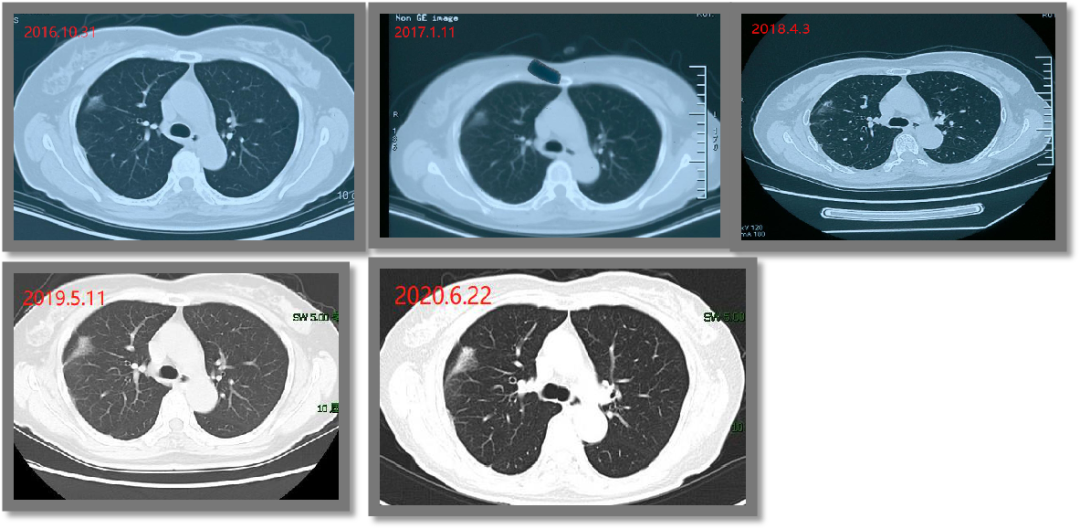

2016年,结节开始变大变实,并出现纤维化,由几个毫米增大到2公分以上。

图1 张女士随访期间的检查结果